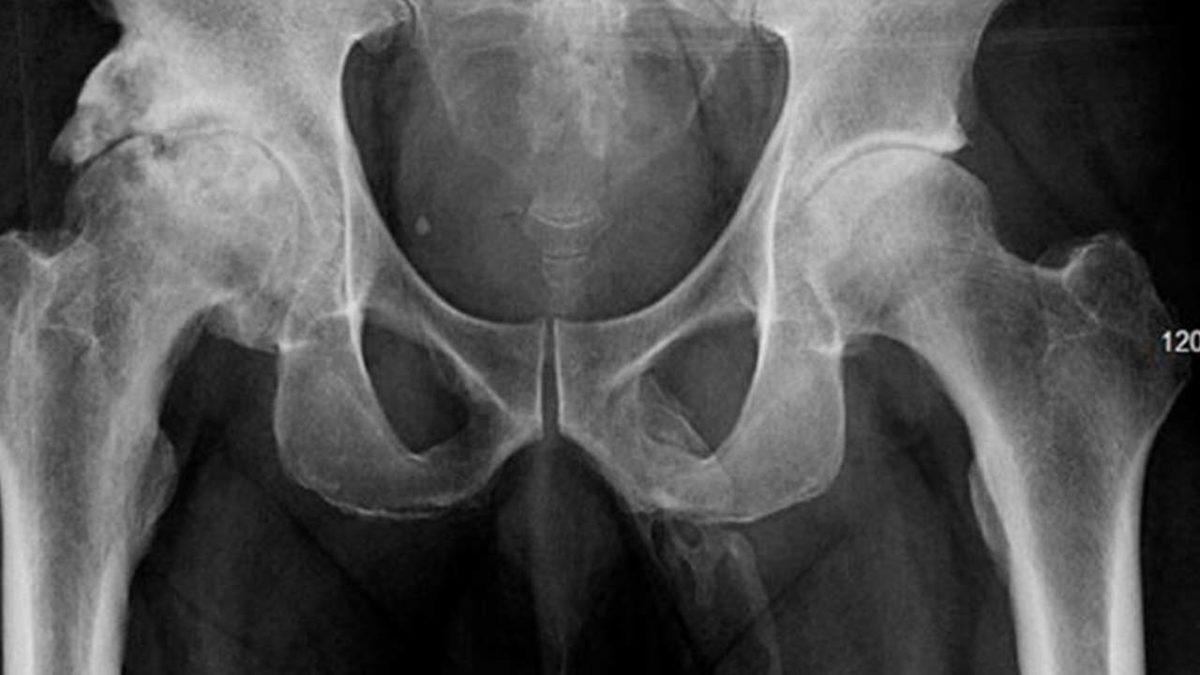

Bazen kemikler olmaması gereken yerlerde gelişebiliyor. 63 yaşındaki bu adamda ise bu durum adamın penisinde meydana geldi. Kalçasının üzerine düşüp acil servise giden adam doktorlara penisinde de acı olduğunu söyledi.

X-ray cihazına giren adamın penisinde ‘kemikleşme’ meydana geldiği görüldü. Sonuç olarak adama ‘penil osifikasyon’ tanısı konuldu. Bu tanı, daha önce medikal literatür boyunca yalnızca 40 kişiye konulmuştu.